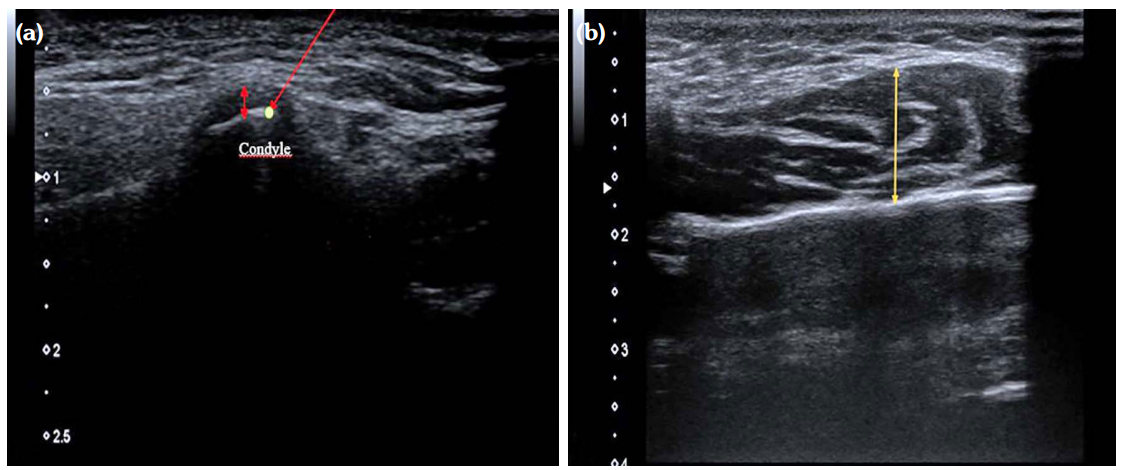

The probe was placed on the TMJ parallel to the long axis of the mandible in an upright sitting position, with their heads free. For both right and left TMJ with the mouth closed; between the condyle and the fossa; a hypoechogenic thin band-shaped area was measured and noted as a disc gap (Figure 2a).

After the thickest place of the muscle was determined by palpating both the right and left masseter muscles, the probe was placed transversely, the mouth was closed and anteroposterior measurement was performed without compression with the probe from the thickest part of the muscle while the muscle was at rest (Figure 2b).

During the USG examination, the effusion displayed as a hypoechoic area in the joint cavity on bilateral TMJ, irregularity on the bone surface, the presence of osteophytes, which are seen as hyperechoic new bone formations with exophytic extension, were evaluated and recorded on the examination form as present or absent. In the TMJ evaluation, flattening and irregularity in bone structures were noted as temporal bone or condyle degeneration.